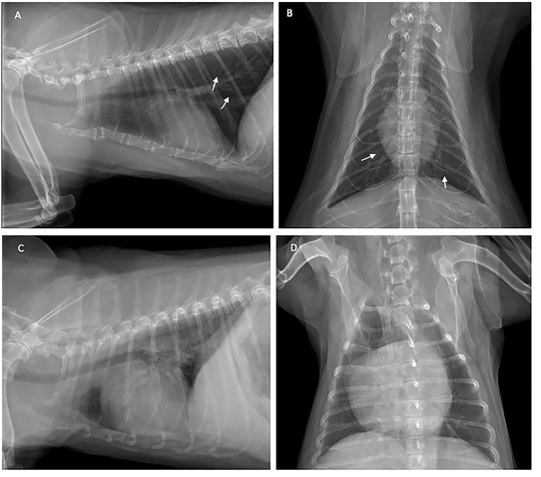

Thoracic radiograph shows the opaque rings of a bronchial pulmonary lung pattern (white arrow) in the cat (A and B), and enlarged heart of the dog (C and D) with heartworm infection.